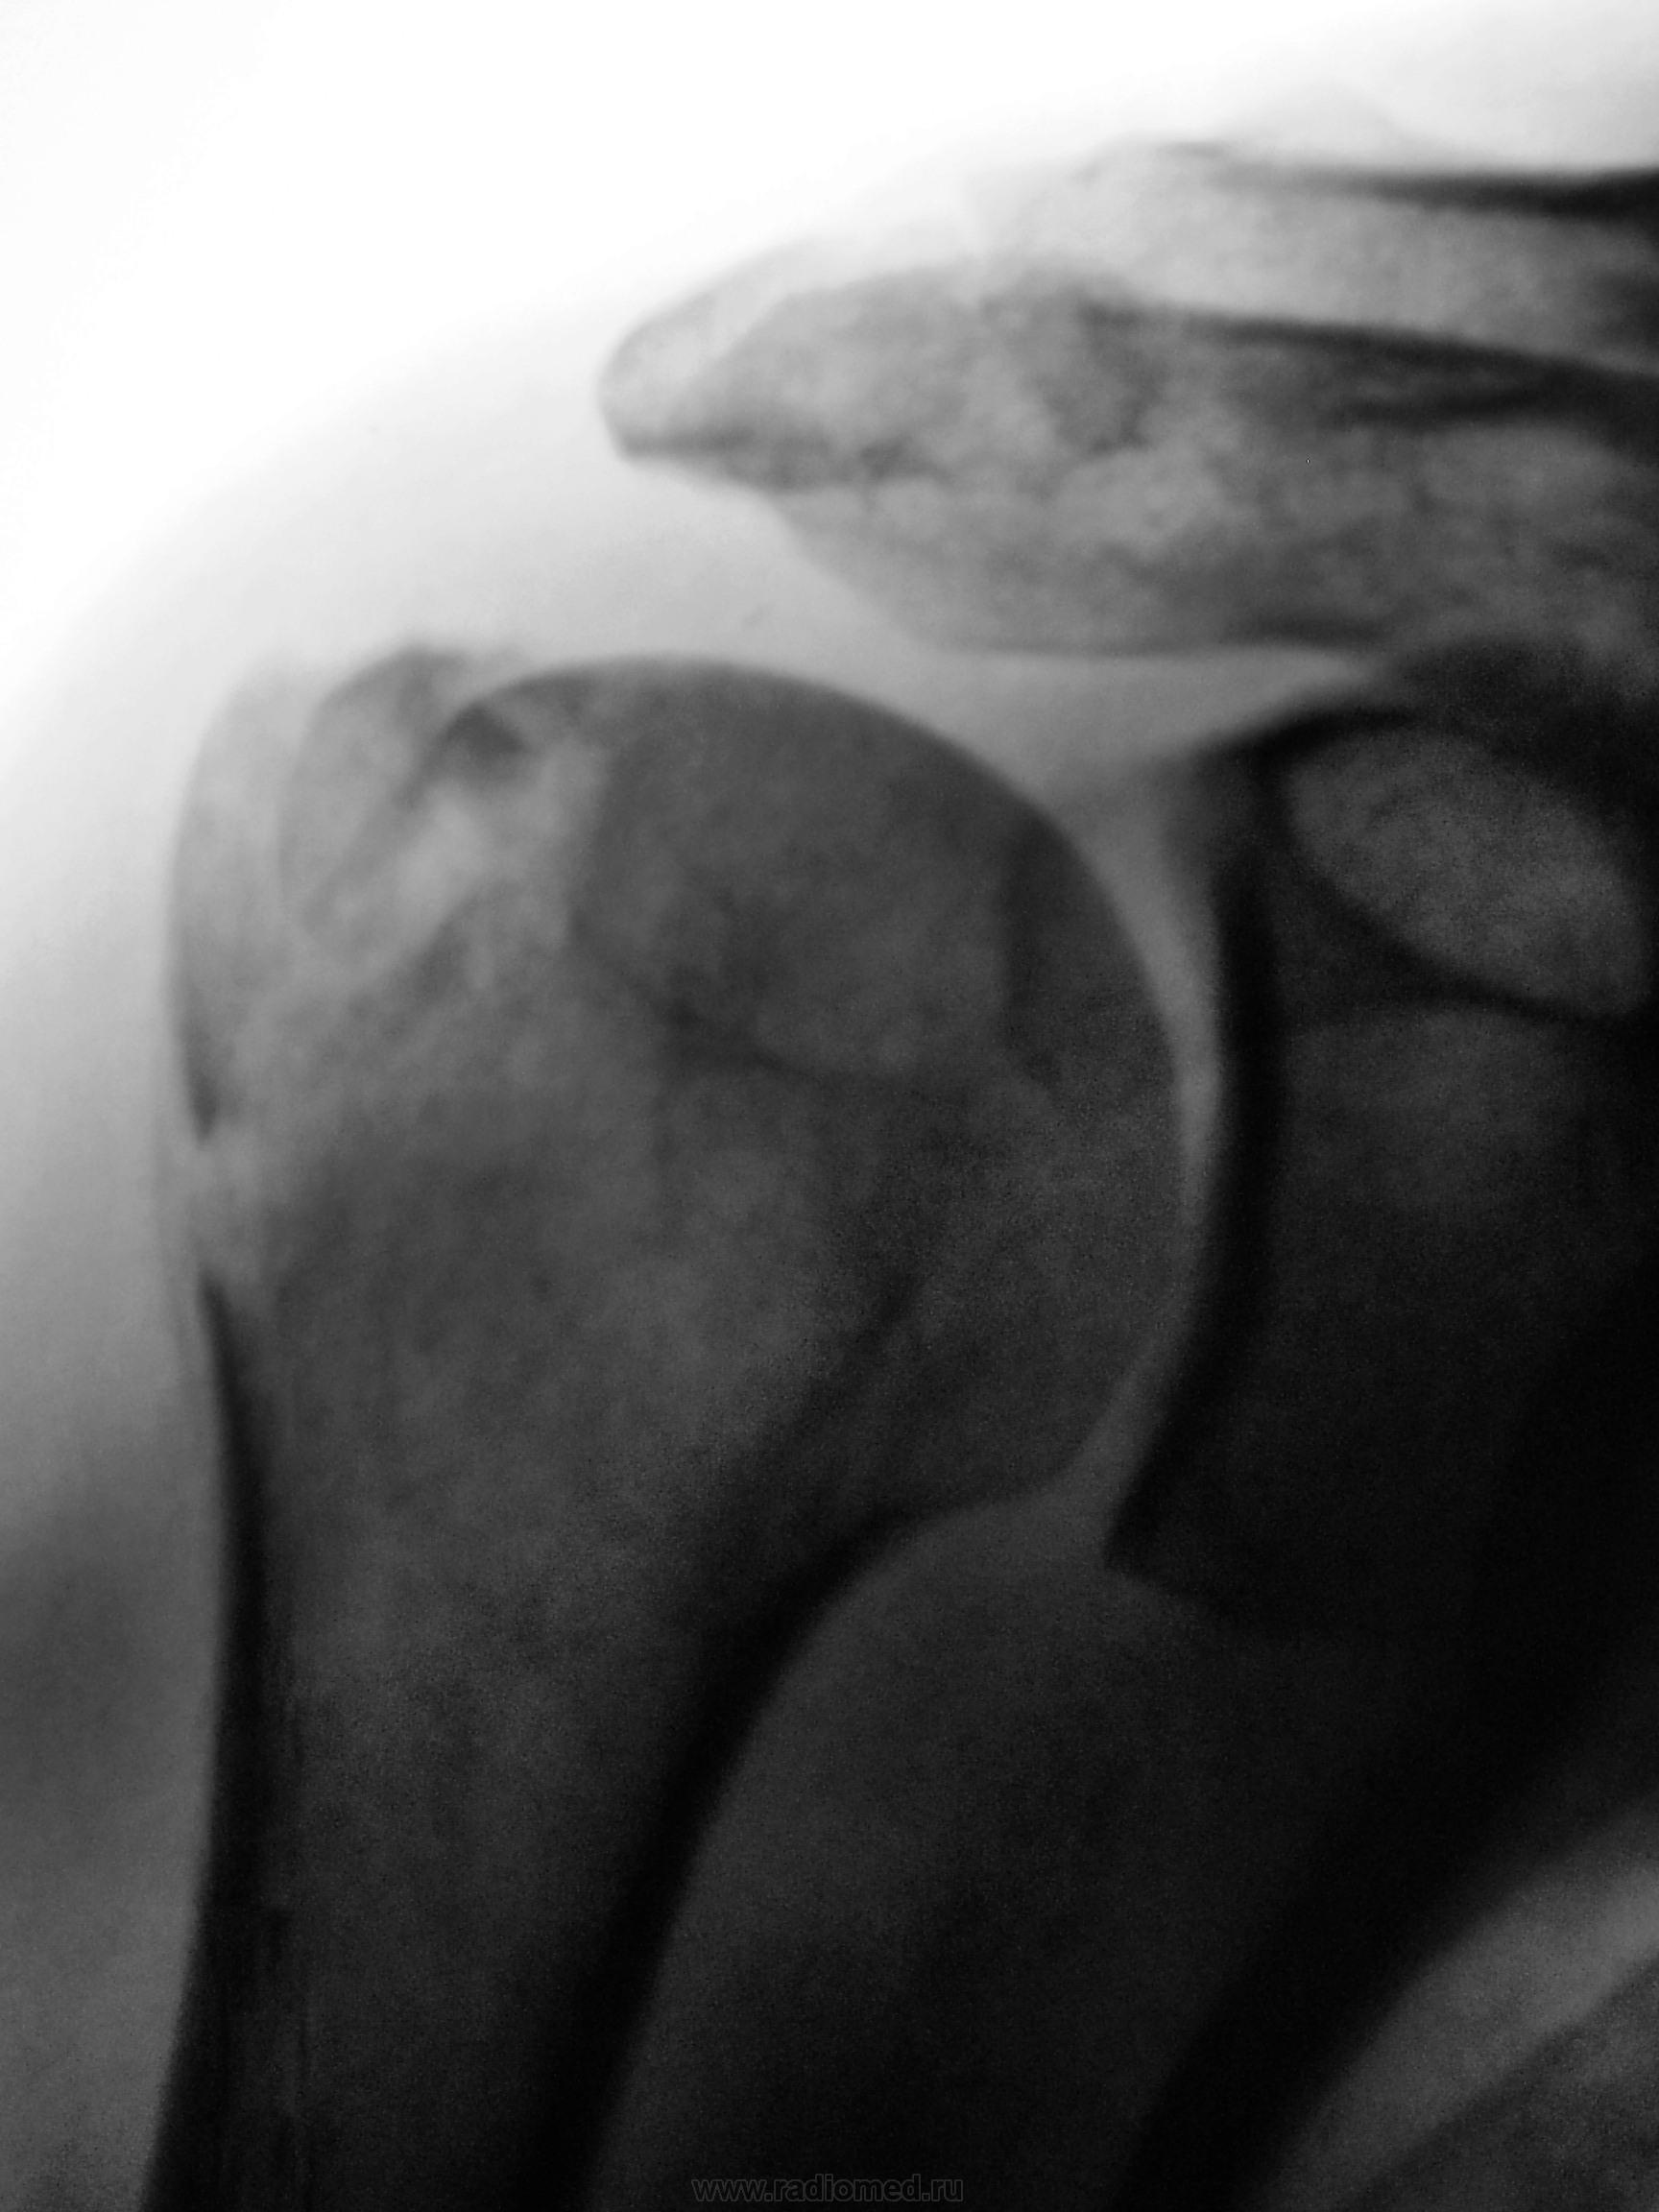

Упал с дерева.

11.p4270017.jpg14.p4270018a.jpg16.p4270019a.jpg19.p4270020a.jpg

Изолированный перелом большого бугорка плечевой кости со смещением на кортикальный слой

В моем понимании это смещение на ширину кортикального слоя ( милиметры ) , т.е. незначительное